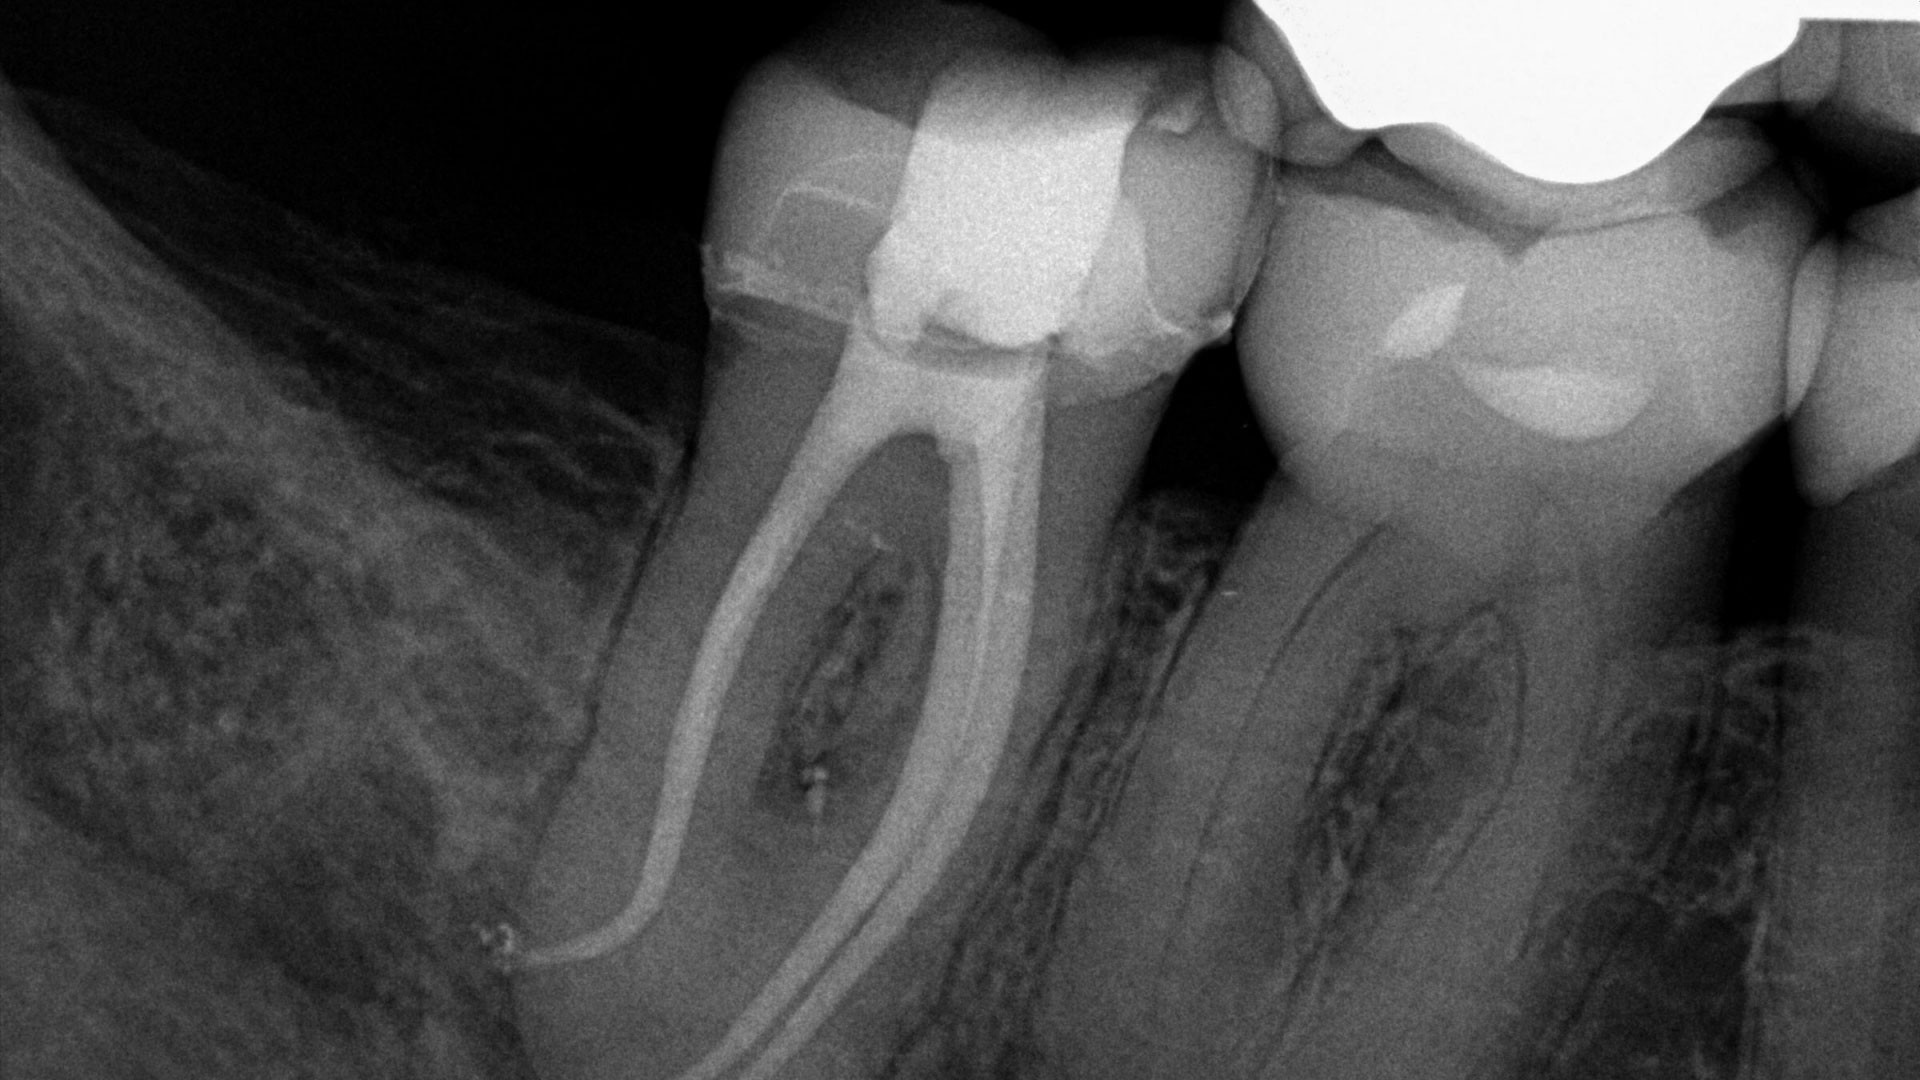

It’s About the Agitation: The Waterlase iPlus Er,Cr:YSGG Advantage in Laser Assisted Endodontics

It has long been established in endodontics that mechanical instrumentation of the canal system is insufficient for proper disinfection. Instead, a combined chemo-mechanical approach is needed whereby mechanical and chemical interactions occur with the pulp and dentin of a tooth.1-3 Infected dentin is removed and shaped with files while irrigating solutions chemically interact with the … Read more

Apicoectomy Performed Using the Er,Cr:YSGG Laser System: A Case Report

Introduction Er,Cr:YSGG laser has been chosen to perform the apicoectomy1,9,13 as an alternative for the use of a scalpel and rotary instruments due to the laser’s precision, lack of vibration16,17 and lack of microfracture occurrence on hard tissues, such as bone and root. Additionally, laser apicoectomy had the benefit of less post-operative discomfort1, capability to … Read more